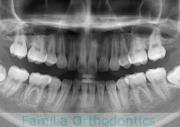

No.23V-132

- 主な症状:

- 開咬

- 年齢:

- 16歳

- 性別:

- 男性

- 抜歯部位

- 上:

- 88

- 下:

- 主な使用装置:

- FEA

- 治療にかかった費用:

- 87万円

開咬なので治療したいとのことで来院されました。受け口傾向のある開咬(前歯が咬み合わない)でしたので、下の親知らずを抜歯してマルチブラケット法にて治療を行いました。約1年半、20回程度の通院が必要でした。開咬は舌の癖の影響が強く、後戻りのリスクが高いケースといえます。